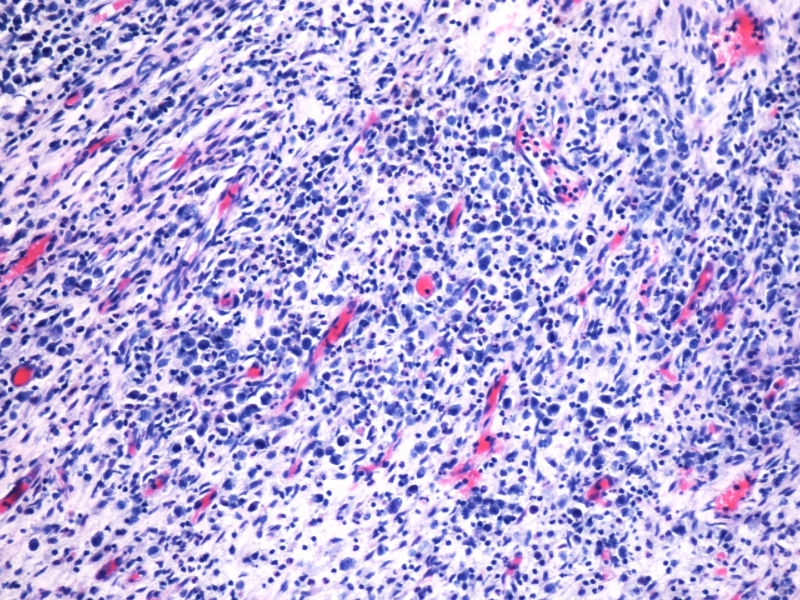

的确如此,CD43不仅表达于多量T细胞淋巴瘤,还可以表达于一些B细胞淋巴瘤,如套细胞淋巴瘤、小淋巴细胞淋巴瘤/白血病、粒细胞肉瘤等等,甚至还可以表达于一些非肿瘤细胞。本例CD2,CD3,CD4,CD8,CD5,CD7均阴性,在这样的大细胞病变形态基础上,此时做CD43和细胞毒标记物只是寻找诊断ALCL的佐证,后来果然CD43和部分细胞毒标志物是阳性,对于“裸”免疫表型的ALCL,这一诊断思路也是WHO和许多文献推荐的,日常工作中也是我们也常常是这样做的。如果病变是在淋巴结内,HE是大细胞病变,且出现上述免疫表型,我想应该有许多病理医生就诊断了ALCL了。只是本例部位等临床特征特殊,诊断需要慎之又慎,但最后ALK-1也显示大细胞阳性,就增加了诊断的信心。

本例全B,全T缺失,使诊断很困难,淋巴瘤范围内一般考虑①HL;②浆细胞分化的肿瘤如浆细胞骨髓瘤或浆母细胞瘤;③ALCL. 以下为鉴别:

ALK阳性ALCL发病年龄,发病部位,细胞形态可以非常广泛。西方国家统计男女比例为1.5:1,主要是40岁以内,尤其是儿童青少年多发。本例46岁女性,流行病学应少见的女性发病时段;

如金老师所言原发于骨也少见,如标题所显示:“临床骶骨脓肿?”表现为骨脓肿恐怕更少,综合以上所以本例的确特殊;

形态学hallmark 细胞显示不是很清晰,大的肿瘤细胞如果在ALCL和HL之间选择可能不容易,但HL的肿瘤细胞形态学特点的范围比较狭窄,而ALCL可能具有更广泛的形态学范围,细胞大小形态以及典型hallmark cell的多少有时很难确定。如果只看HE,觉得ALCL的可能会安全一点,当然我个人经验不足,可能理解得比较肤浅。

本例CD68的表达也许很重要,HL可以有严重的炎症背景,但背景细胞是否会出现如此明显CD68阳性细胞,还请各位老师教我;而ALCL CD68大概可以阳性。另外就是哪些细胞是肿瘤细胞的问题了,可能未必局限于CD30阳性的大细胞吧。